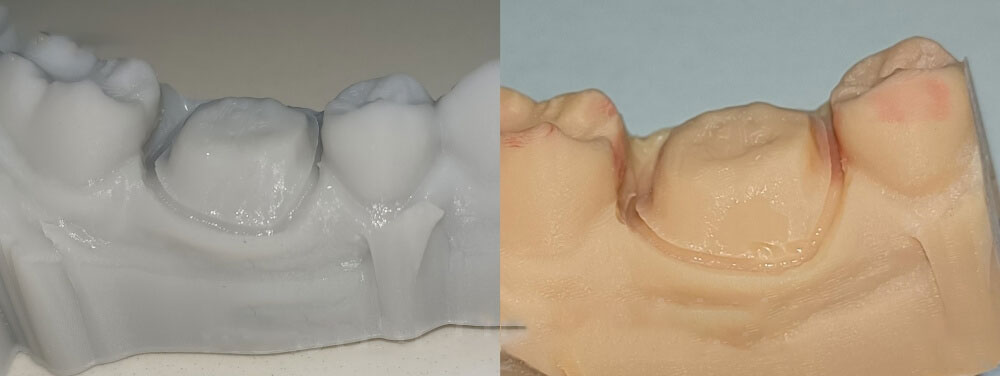

4. Printing 3D models

We printed working model with one brand of printer, and printed study model with another brand of printer. Our crown should perfectly seat on both working models and study models. This means that if one brand of printer is having a problem with precision, we will immediately know. It makes sure that the our 3D models are precise, and it also makes sure that our crowns are with precise margins.

The grey color 3D printed model is working model, while the oringe one is study model.

5. Checking new margin

As we can see, the margin of the full zirconia crown is perfect on the working model and the study model.

Full zirconia crowns